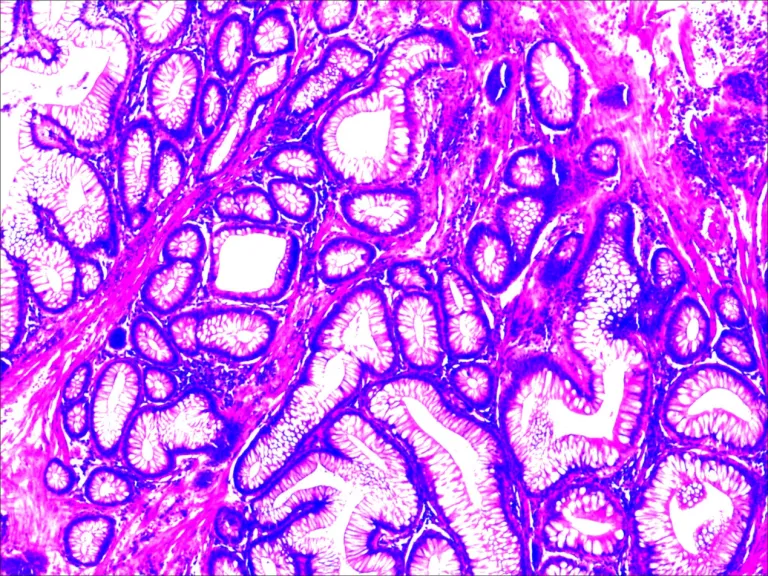

病理科副主任王强在阅片过程中,发现该病理组织其中一枚息肉的形态与常见息肉不同:病变中伴树枝状伸长的平滑肌,周围有增生的非肿瘤性黏膜。根据该形态学表现,王强医生想到了罕见病黑斑息肉的可能性。